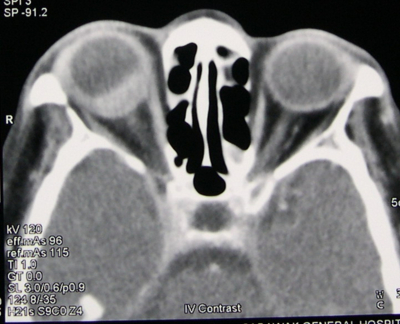

The patient was initially thought to have right indirect carotid-cavernous fistula. We ordered an urgent CT orbit and brain (Figure 4). The right globe was proptosed with uveal thickening which was most pronounced in the posterior wall. The lesion enhanced homogenously with intravenous contrast agent. The medial and lateral recti were thickened as well. The retro-orbital fat was normal, there was no retro-orbital tumor, the cavernous sinus was not enlarged and there was no dilatation of the superior ophthalmic veins.

Figure 5